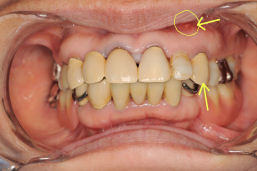

下の5番目の歯が先天的に欠損しており、そのため子供の歯が骨に癒着しており、側方が噛まない状態になっていました。

マルチループというワイヤーを使い、すべての歯を本来あるべき位置に戻しました。1.5年後です。(中段)5番目の歯以外はすべてきちんと噛みあいました。5番目の乳歯を抜いてインプラントも一つの手ではありますが、まだ若い年齢と骨に癒着しているということを考え合わせてその乳歯の上に土台を作って白い歯をかぶせました。4年後の今でもきちんと機能しています。

矯正前

矯正直後

矯正後4年